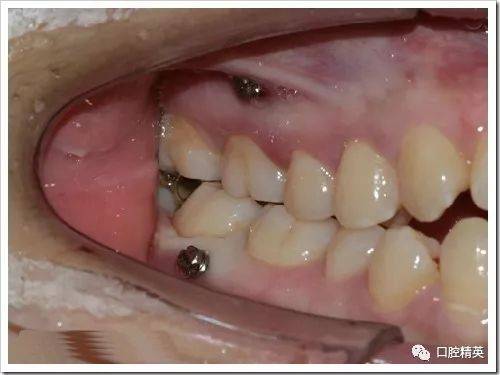

| 植入钉体 | 将微种植钉(钛合金)旋入骨孔,直至头部露出牙龈约1-2mm(便于后续挂橡皮圈)。 | 钉体植入后的三维位置图(展示与牙根、牙槽嵴的关系)。 |

- 植入位置:常见于上颌后牙区(颧牙槽嵴)、下颌后牙区(外斜线)、腭部(腭中缝)。